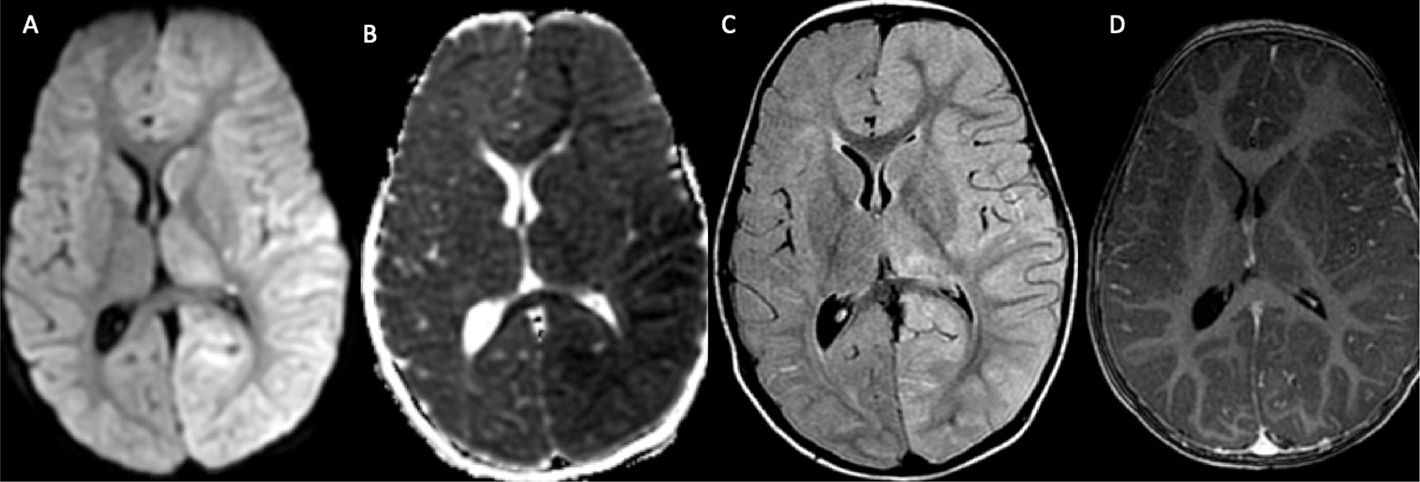

Perfusion imaging (DSC) is useful to identify regions of relative ischemia that are at risk for infarction in moyamoya syndrome and to assess changes in perfusion after therapy. Increased capillary mean transit times and macrovascular delays (e.g., time-to-maxima) may be the result of arterial stenoses or the development of moyamoya collateral vessels (Figure 7) (98). An increase in mean transit time associated with reduced cerebral blood volume or with a lack of increase in cerebral blood volume after administration of intravenous acetazolamide is more suggestive of tissue at risk; although, in the non-acute setting, benign, compensated oligemic delays cannot be discriminated from regions of severe hemodynamic stress with exhausted cerebrovascular reserve, and in this setting, cerebrovascular reactivity or direct oximetry may be required for meaningful prognostication (99).

Fig 7

Figure 7. A 17-year-old female who presented with an episode of left facial droop and difficulty speaking. DWI (A) with corresponding ADC (B) and FLAIR (C) MR images demonstrate an acute infarct (arrow) in the left frontal lobe with additional remote infarcts in the bilateral frontoparietal white matter, more on the right than the left. MRA (D) demonstrates occlusion of the right ICA terminus and proximal right ACA and MCA with associated collaterals (circle). DSC perfusion mean transit time (MTT) map (E) demonstrates prolonged MTT in the right middle cerebral artery territory. MTT perfusion map after encephaloduroarteriosynangiosis (F) demonstrates improved, now symmetric transit times between cerebral hemispheres.